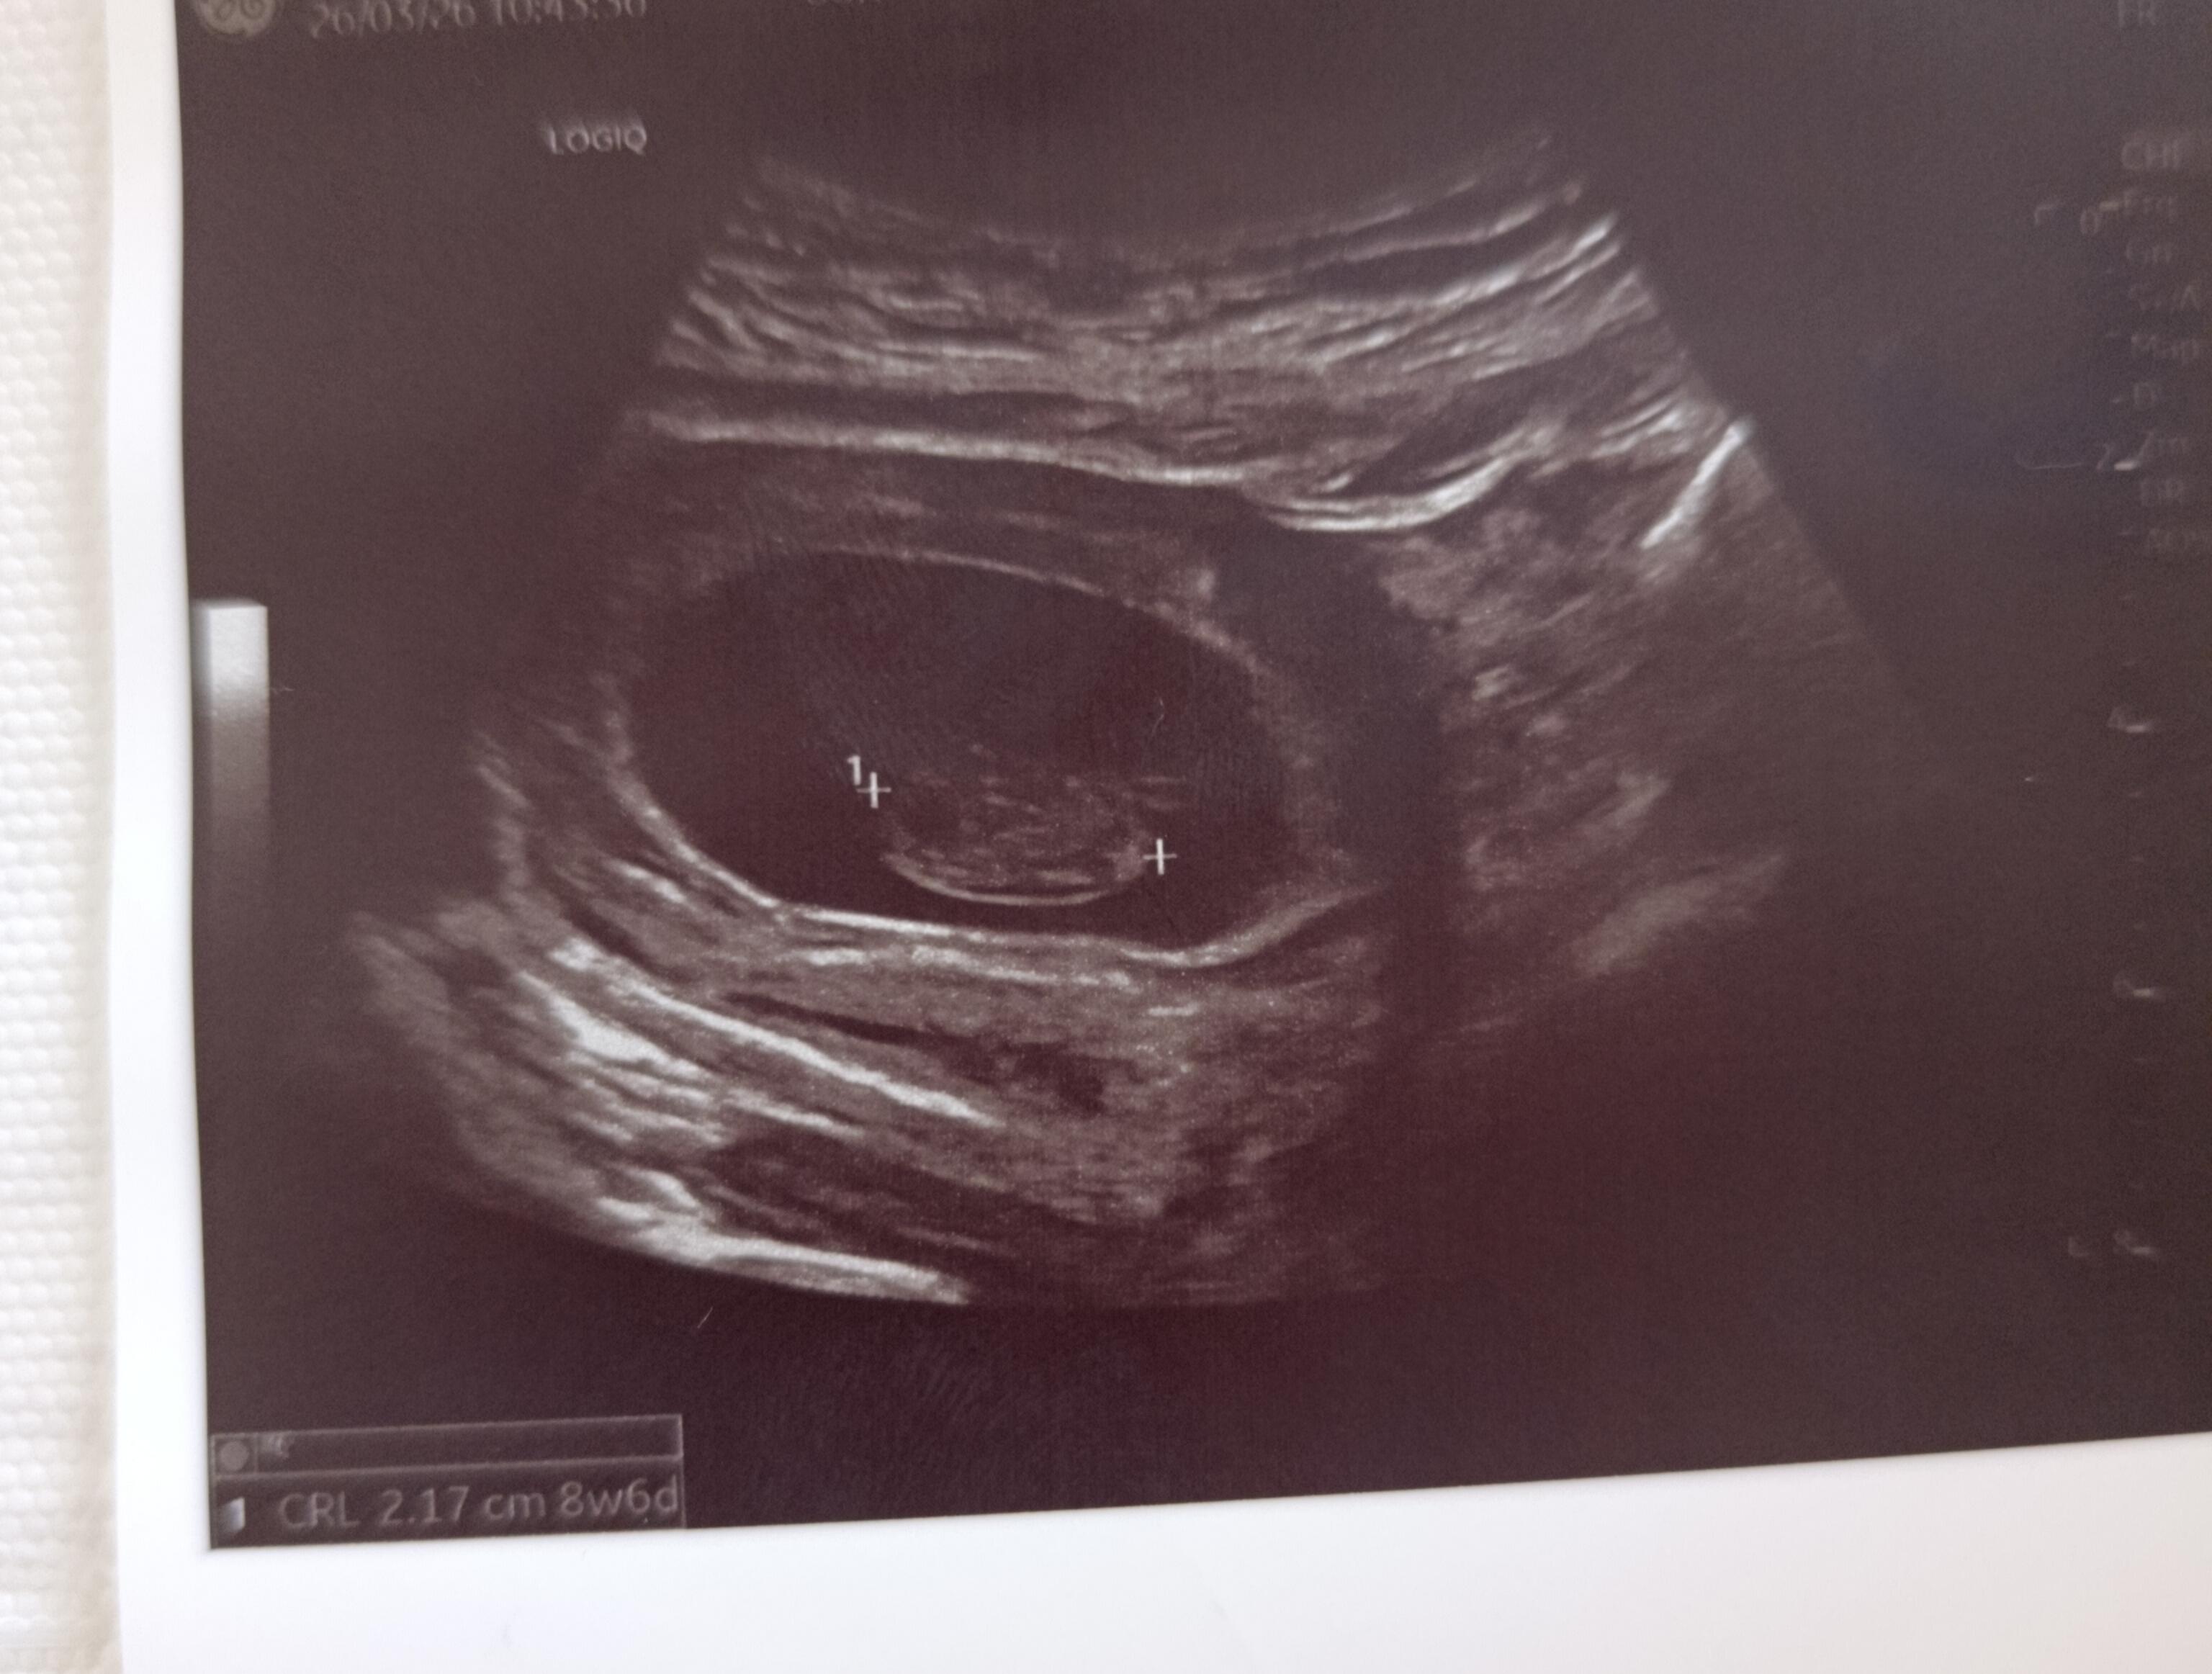

Hep ben tahmin yapıyordum kızlar şimdi ben sizden tahmin bekliyorum Bizim cinsiyetimiz ne teyzeler yorumlarınızı bekliyorum…

Allah nasip ederse inşallah 4. gebeliğim canım